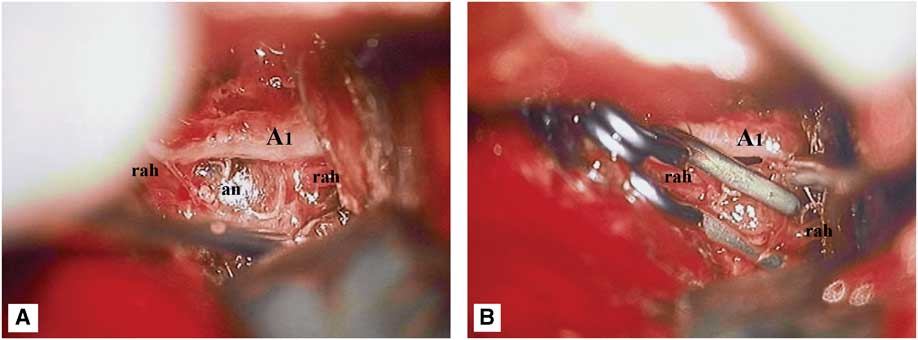

Given the location and configuration of the aneurysm, endovascular embolization was not felt to be a good treatment option. In fact, given the dissecting fusiform nature of the aneurysm, preservation of the RAH would have been virtually impossible by endovascular means. Although, not infrequently, RAH occlusion may only cause clinically silent infarctions, severe neurological deficits have nonetheless been observed in this setting.Reference Rhoton 5 Likewise, the small size of this vessel and its sharp angle of takeoff from the ACA would have made superselective catheterization very technically challenging and increased the risk of microwire perforation and intraprocedural rupture. Thus, the decision was made to surgically explore the aneurysm and attempt clip reconstruction of the RAH. Under continuous intraoperative neurophysiological monitoring (motor-evoked potentials), the aneurysm was exposed via a standard left pterional transsylvian approach. The aneurysm had a fusiform, pearl-on-string appearance and was much larger than its angiographically visible portion. There was an obvious intramural thrombus impinging on the underlying A1 vessel (Figure 3A). The aneurysmal dome was dissected circumferentially and then the RAH was clip-reconstructed using two side-opening Yasargil clips that were placed parallel to the vessel, along the long axis of the aneurysm (Figure 3B; Video). Unfortunately, intraoperative angiography demonstrated that both the aneurysm and the RAH were completely obliterated by the clip (Figure 1G). However, intraoperative motor-evoked potentials remained normal, suggesting that a left internal capsular infarct was unlikely to occur despite occlusion of the RAH. Thus, the aneurysm clips were left in place.

Figure 3 Intraoperative microphotographs demonstrating the dissecting aneurysm (an) of the left recurrent artery of Heubner (rah). (A) Note the large intramural thrombus impinging on the underlying A1 vessel. (B) Attempted clip reconstruction of the recurrent artery of Heubner, using two side-opening Yasargil clips.